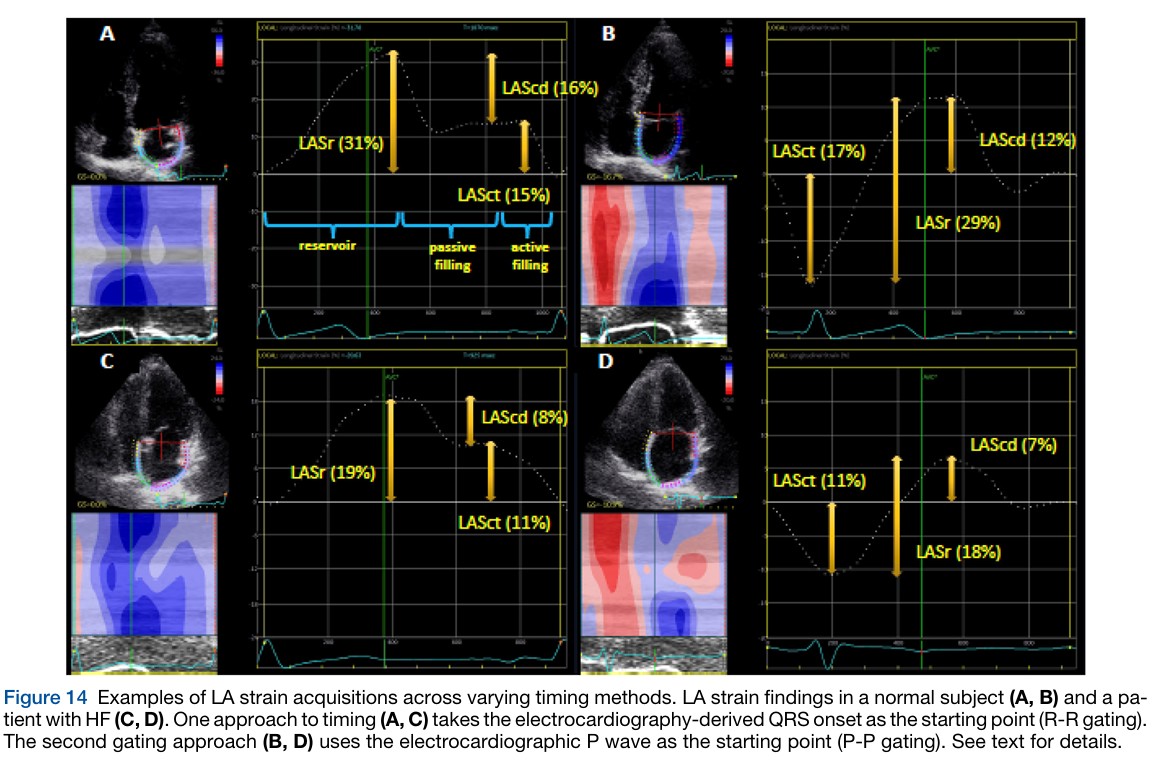

Leia maisFunção do Átrio Esquerdo na MAC: análise pelo strain cardíaco